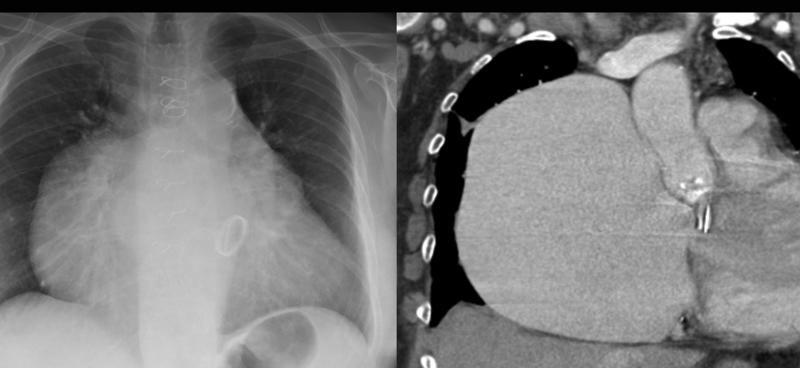

Gallery Cardiac Other Giant RA CT

Giant RA CT